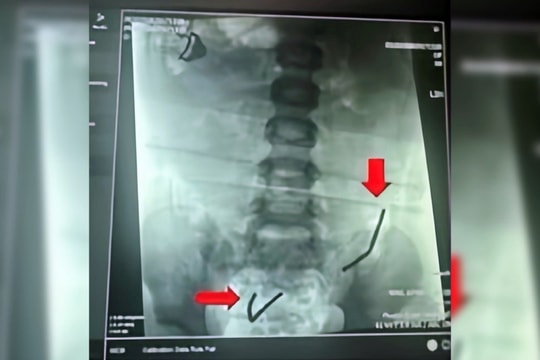

Hi hữu: Đinh phẫu thuật 'lang thang' trong lồng ngực bệnh nhân

05/09/2025 08:24

Bệnh viện Đa khoa tỉnh Quảng Trị vừa tiếp nhận và điều trị thành công một trường hợp dị vật kim loại di chuyển vào phổi rất hiếm gặp, tiềm ẩn nguy cơ đe dọa tính mạng.